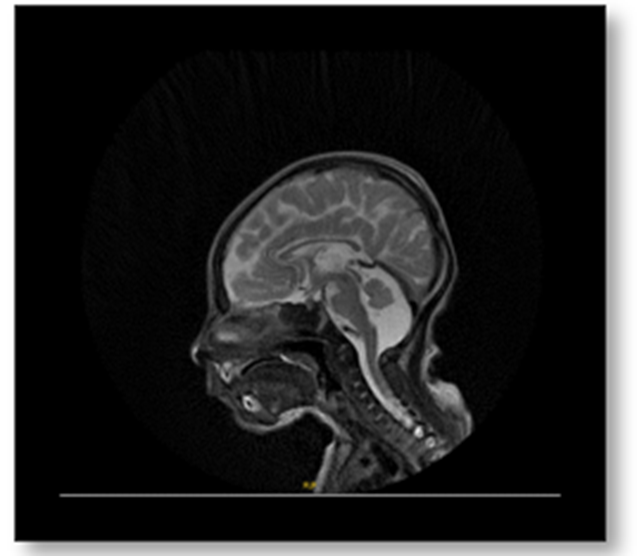

The infant exhibited persistent myoclonic and focal seizures refractory to treatment with levetiracetam, clonazepam, phenobarbital, and carbamazepine. Clinical examination revealed global developmental delay and hypotonia. Following genetic diagnosis, supplementation with CoQ10 (71 mg three times daily) and pyridoxal-5-phosphate was initiated. Brain MRI showed a large retrocerebellar space with a cerebrospinal fluid signal and a normal cerebellar vermis (Figure 1).

Figure 1: Brain MRI shows large retro cerebellar space that follows CSF signal on all sequences. Normal cerebellar vermis.

The patient’s clinical presentation—refractory seizures, lactic acidosis, hypotonia, failure to thrive, and early-onset cardiomyopathy—was consistent with previously reported neonatal-onset COQ10D5 cases [3–5]. The persistent metabolic acidosis and elevated lactate reflect mitochondrial dysfunction, while the neuroimaging findings of mega cisterna magna and subependymal cysts may represent structural vulnerabilities resulting from in utero mitochondrial stress [6]. Neurological manifestations are particularly severe in COQ10D5 due to the high energy dependence of the central nervous system.